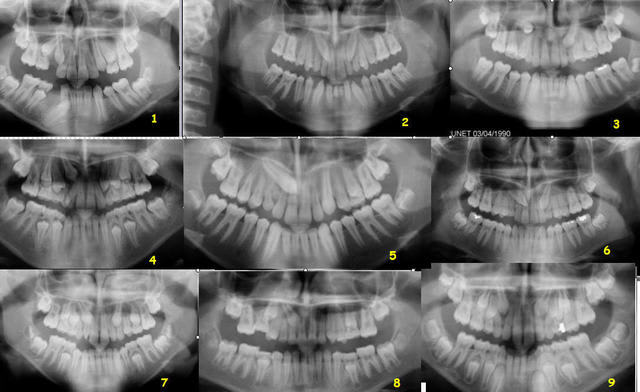

OK, faisons un "quiz".

De 1 à 9 :

1 - 13 V ou P ? - 43 V ou P ?

2 - 13 V ou P ? - 23 V ou P ?

etc.

A toi, alexlop. Tu peux demander de l'aide aux autres, bien entendu.

Daniel

mais pour le jeu:

1 - 13 V et 43 L

2- 13 et 23 couronne V

3- 13 et 23 P

4 - 13 P

5- 13 P

6- 13 23 P

7- 13 P 23 V

8- 13 P

9- 13 23 P

alors ?